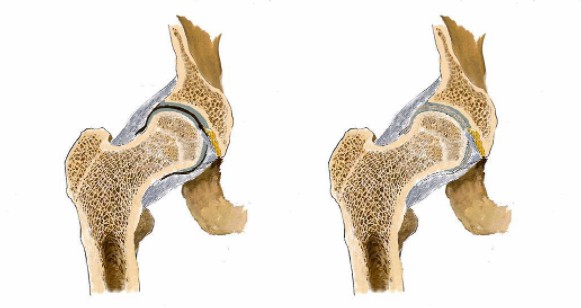

看男孩不說話,醫(yī)生繼續(xù)說道:“你的HLA-B27顯示陰性,如果是陽性就可以確診是強直性脊柱炎,現(xiàn)在只能排查……如果確診是強直性脊柱炎,就要就要及早治療,因為這個病是不可逆的,我們只能延緩它病程進度……”

“你這沒事!腿痛就是有點水腫炎癥導致的,注意休息鍛煉適度就會好的。”